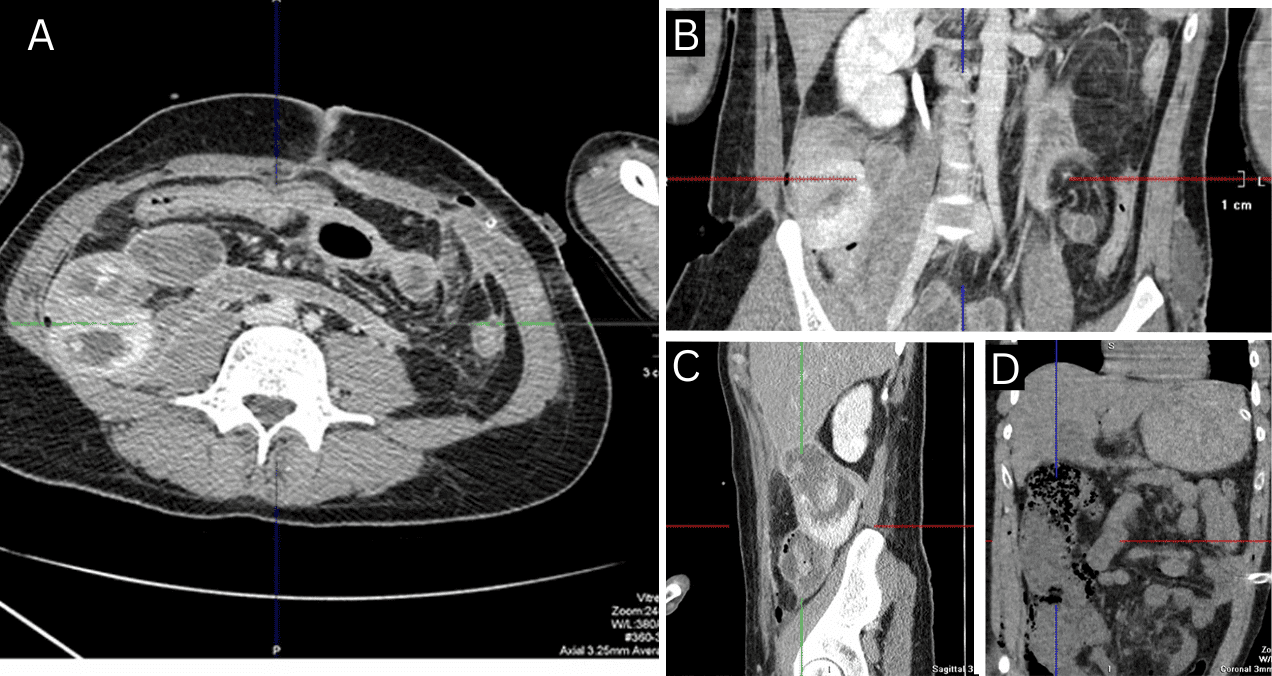

Se efectuaron suturas en las zonas lesionadas del tracto intestinal, empaquetamiento abdominal y formación de laparostomía. Cuatro horas después del evento, el paciente fue trasladado al hospital de Rol 4 del Ministerio de Defensa en Járkov, donde se completó su evaluación con exámenes de laboratorio y tomografía computarizada abdominal.

Durante los primeros días de hospitalización, el paciente fue sometido a múltiples procedimientos quirúrgicos. Al segundo día, se realizó una relaparotomía por sospecha de compromiso tisular. En esta revisión se identificaron signos necróticos en el ciego, el colon ascendente y los 70 cm distales del intestino delgado, lo cual llevó a una resección amplia con anastomosis ileoascendente y drenaje abdominal.

Los autores (Lurín) relatan que el día 25 se detectó una nueva perforación intestinal. En la cirugía se encontró una úlcera de 0,5 × 0,5 cm en el yeyuno, a 10 cm del ligamento de Treitz, con bordes regulares y sin sangrado activo. Se realizó su resección, cierre primario e intubación yeyunal. La laparostomía se mantuvo abierta debido al alto riesgo de recurrencia. La histopatología confirmó el diagnóstico de enfermedad de Crohn.